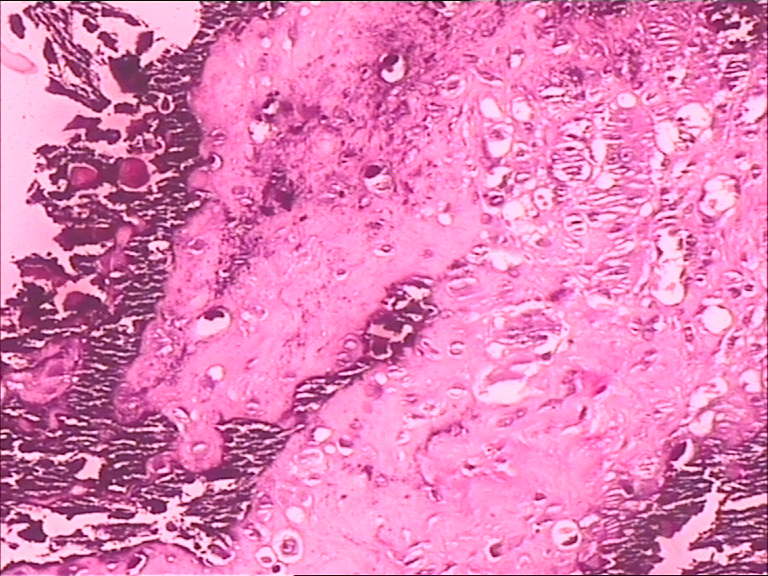

腰部皮下肿块

性别

女

年龄

44岁

临床诊断

腰部皮下肿块待查

一般病史

发现腰部肿块一年,渐增大,无压痛,无红肿。

标本名称

腰部正中偏右皮下肿块

大体所见

肿块大小3*2.5*1.5cm,未见明显包膜,切面灰白、灰黄,可见部分钙化。

图2

是否考虑钙化性腱膜纤维瘤

瘤样钙盐沉着